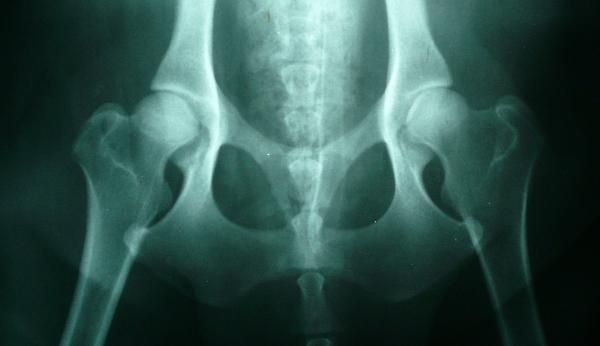

Displasia de cadera

La displasia de cadera es una enfermedad ósea, hereditaria, no congénita puesto que no se manifiesta en el nacimiento, sino que se desarrolla con el crecimiento del cachorro y puede aparecer a partir de los 4 ó 5 meses de edad, y además es degenerativa; producida por una malformación de la articulación coxofemoral (unión del acetábulo de la cadera y la cabeza femoral); que puede producir dolor e incluso cojera en el animal que la padece, y dificultad para sentarse o subir escaleras. La edad de presentación varía entre los 4 meses en los casos más extremos y 12 meses. Sin embargo, antes de los 4 meses se puede realizar el test de PennHip donde se podrá precisar las probabilidades para que un cachorro desarrolle displasia, pero nunca diagnosticarla ya que no es hasta los 4 meses cuando hay un desarrollo suficiente de las mismas. Los casos de displasia de cadera, por lo general, suelen ser bilaterales.

La gravedad de la displasia se puede medir si trazamos el denominado ángulo de Norberg. Éste consiste en trazar sobre una radiografía una línea que vaya desde el centro de una cabeza del fémur, al centro de la otra. Posteriormente, desde ambos extremos se traza otra línea que pase por el borde acetabular dorsal, formando así un ángulo con la anterior. Según la amplitud del ángulo, tenemos que:

No se presenta displasia si es mayor de 105º.

Si mide entre 100-105º, el animal tiene displasia leve.

Si mide entre 90-100º, la displasia es moderada. Se acompaña de enfermedad degenerativa articular y aplanamiento del acetábulo.

Si mide menos de 90º, la displasia es grave. Puede llegar a presentar luxación.